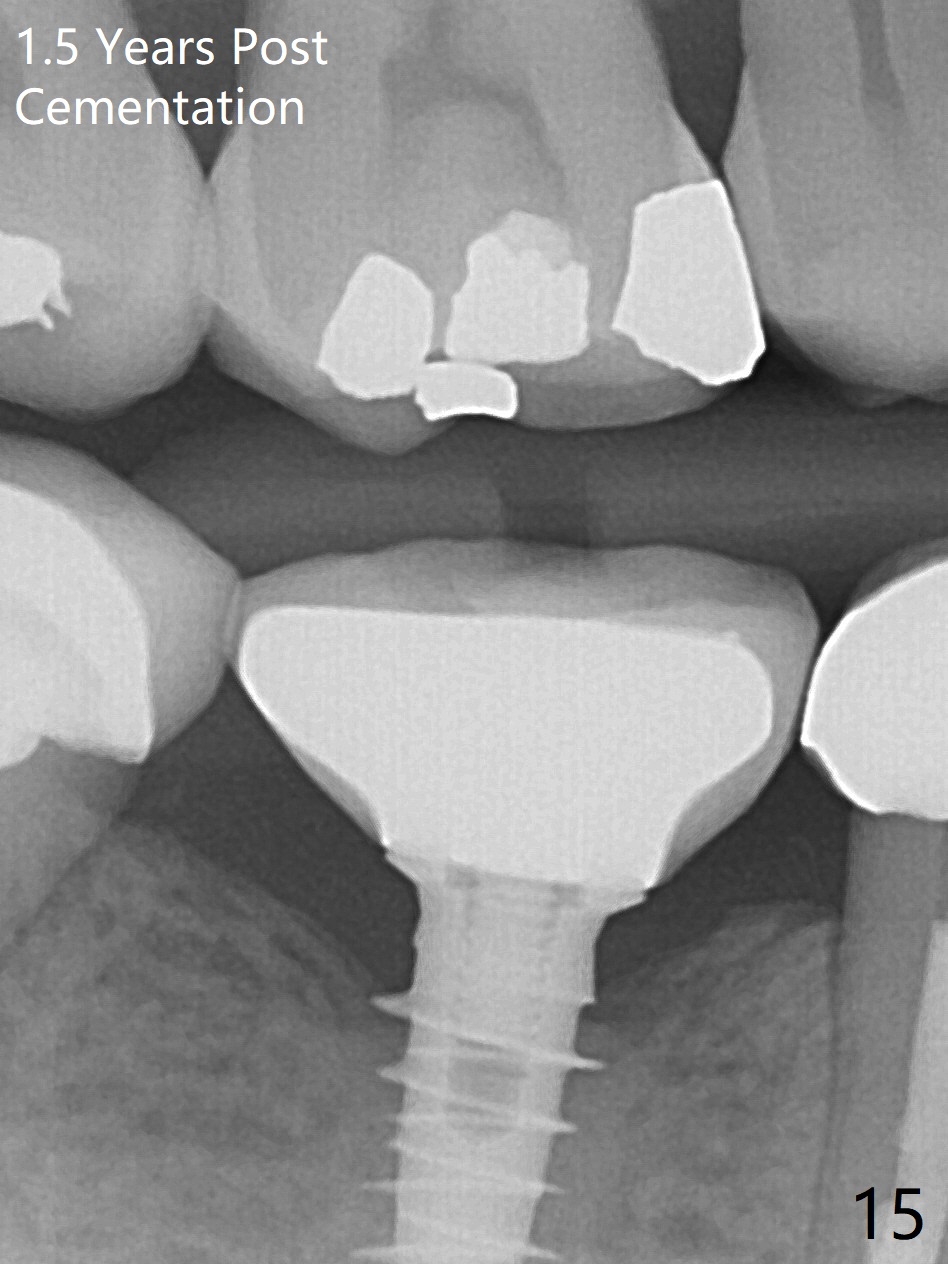

Splinted provisional is fabricated #30 and 31 one month postop. The patient returns for final restoration (single units) nearly 4 months postop (Fig.11). Since the margin is subgingival, a screw type crown is fabricated for #30 (Fig.12). The buccal gingiva looks convex after healing cap removal (Fig.13, as compared to Fig.4 (concave)). PA is taken immediately post tightening and cementation (Fig.14, 5 months postop). It appears that new bone has grown between the most coronal threads (arrows). The bone density immediately around the implant appears to increase 1.5 years post cementation (Fig.15,16). She returns because of failure of 18-20 bridge (implants will be placed at 18/19). The implant at #30 is in fact not placed deep enough; the coronal threads seem to be exposed, although there is no periimplantitis (Fig.17 CT). The tooth #31 is symptomatic; the mesial canal is missing (Fig.18 M, <). The gingiva around the crowns at #30 and 31 remains healthy 2 years 4 months post cementation (Fig.19). Metal exposure of the crown at #31 is intentional. Occlusal reduction is done to alleviate periapical re-infection (Fig.18).